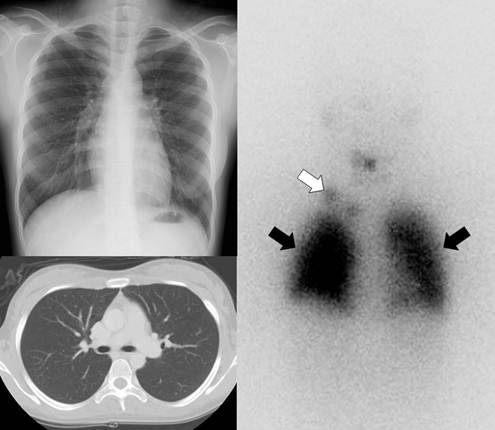

Gamma camera imaging with radioiodine (I-131 or I-123) can visualize metastatic lesions in differentiated thyroid cancer patients who have undergone total thyroidectomy because the lesions are highly efficient at trapping circulating iodine by expression of NIS (Fig. 2) [25]. Radioiodine scintigraphy, once the mainstay of post-therapy imaging surveillance, has largely been replaced by neck ultrasonography as the modality of choice for long-term imaging surveillance, although it still may be used for the detection of occult or distant metastases, particularly in the setting of a newly elevated serum thyroglobulin level [26]. Routine use of radioiodine scintigraphy for surveillance is not recommended for low-risk patients. However, it is still used in patients with intermediate or high risk of recurrence, as well as to assess patients for evidence of recurrence in the setting of an elevated thyroglobulin level with a negative neck ultrasonography. Scintigraphy performed after empiric treatment with high doses of I-131 is more sensitive than the usual diagnostic I-131 scanning [26].

Figure 2

A 21-year-old female who underwent total thyroidectomy due to papillary thyroid cancer. Chest simple radiography and CT did not demonstrate any metastatic lesion of the cancer in the neck and chest regions. However, a radioiodine whole body scan revealed lymph node metastases (white arrow) in the right supraclavicular area and diffuse lung metastases (black arrows).